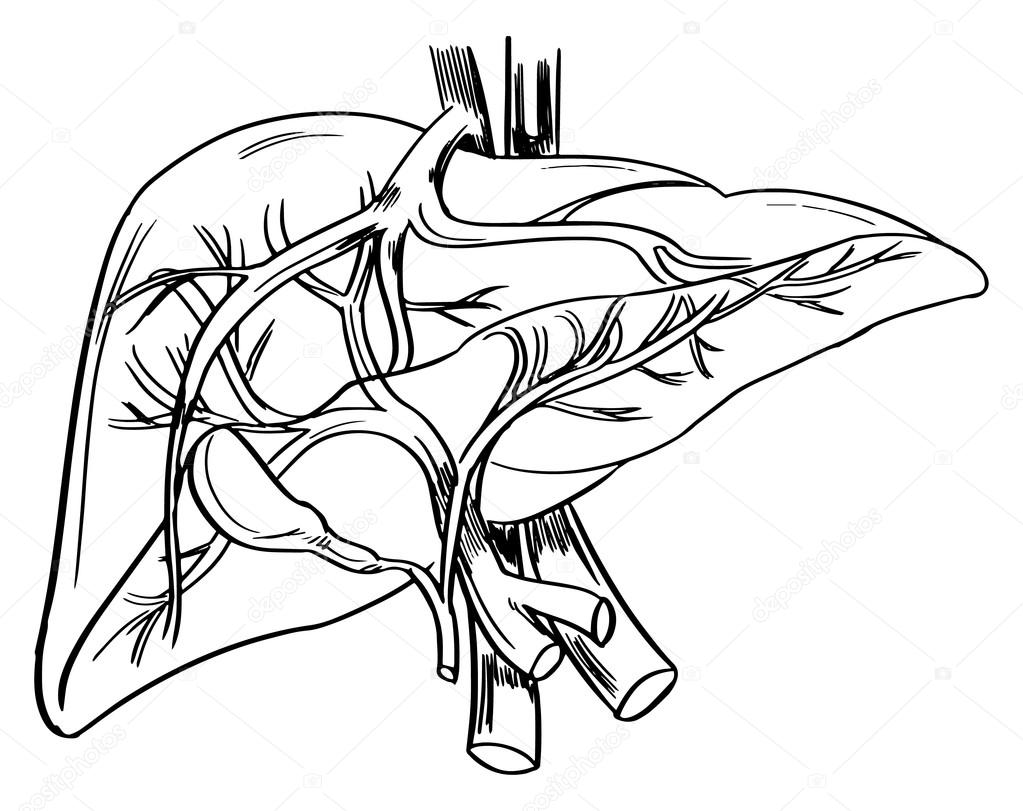

Печень, один из самых крупных и важных органов человеческого тела, выполняет множество жизненно необходимых функций, включая фильтрацию токсинов и производство жизненно важных белков. В данной статье мы рассмотрим, как наглядные изображения печени могут помочь лучше понять её структуру, функции и возможные заболевания. Использование рисунков и диаграмм делает сложные биологические процессы более доступными для понимания, особенно важно это для студентов, врачей и пациентов, стремящихся глубже изучить этот ключевой орган.

Печень рисунок